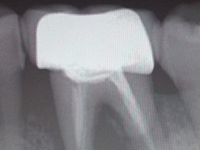

除净病变组织,保护牙髓和健康牙齿组织,建立良好的固位形和抗形,以免造成继发龋。

早龋,一次消毒即可进行补牙,中龋或深龋,则需m三至五次,如果涉及到牙神经则需根管治疗。